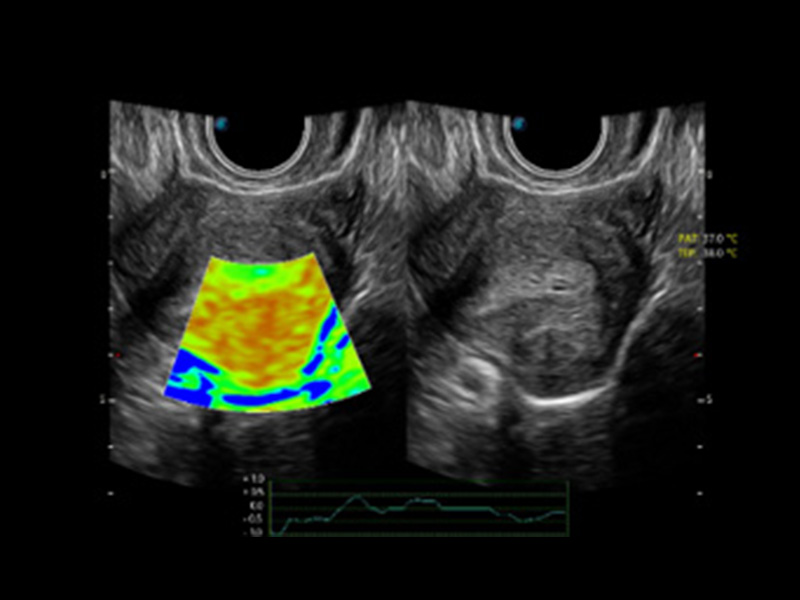

4D HyCoSy mit SPI

Erhöhte Leistungsfähigkeit für mehr Herausforderungen bereit

Die farbkodierte Hysterosalpingo-Kontrastsonografie (HyCoSy) ist eine proprietäre Funktion auf P60 Exp, die die Ankunftszeit von Kontrastmitteln in verschiedenen Teilen der Gebärmutter, der Eileiter und der Eierstöcke klar demonstrieren kann. Dadurch erhalten Kliniker starke und zuversichtliche Beweise, um die Tubenpatenz bei subfertilen Frauen zu untersuchen.

• Eileiter mit 4D HyCoSy

• Eileiter mit 4D HyCoSy mit SPI